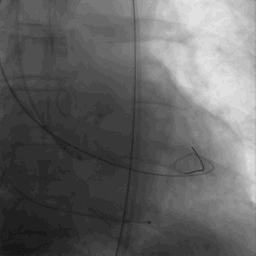

瓣膜定位

瓣膜释放

瓣膜释放后

瓣膜释放后形态位置良好,造影无返流。